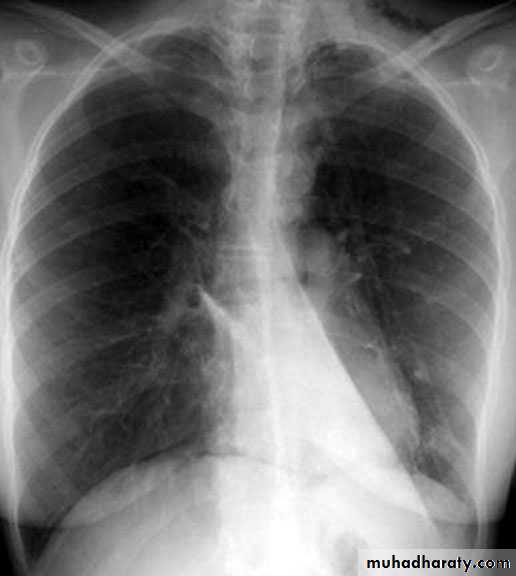

Left upper lobe collapse

Complete rt. & left Lung collapse